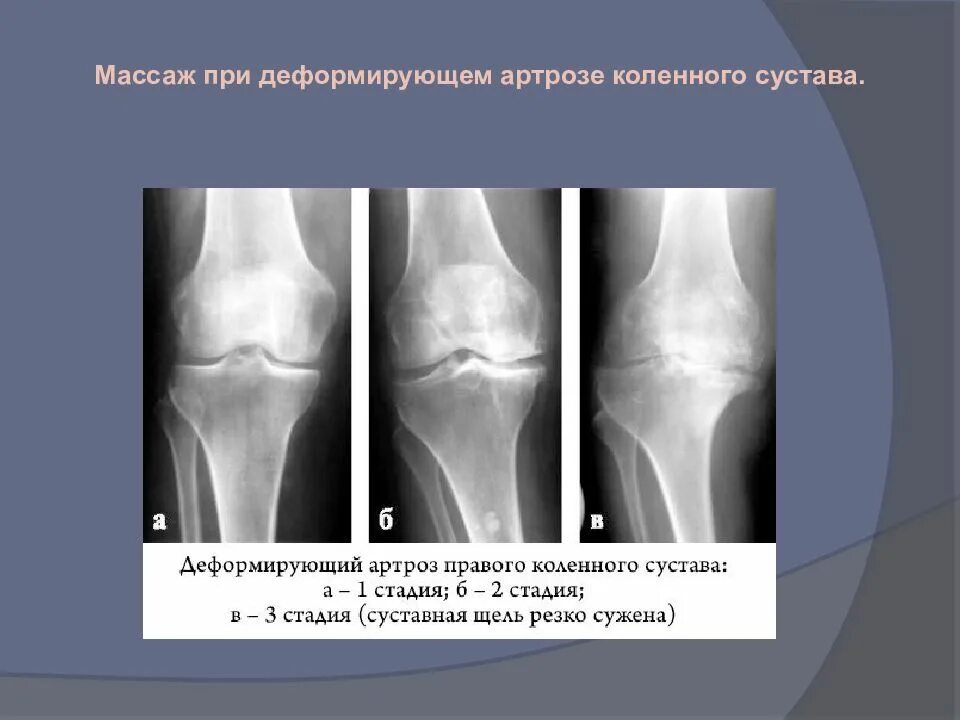

Деформирующий артроз коленных